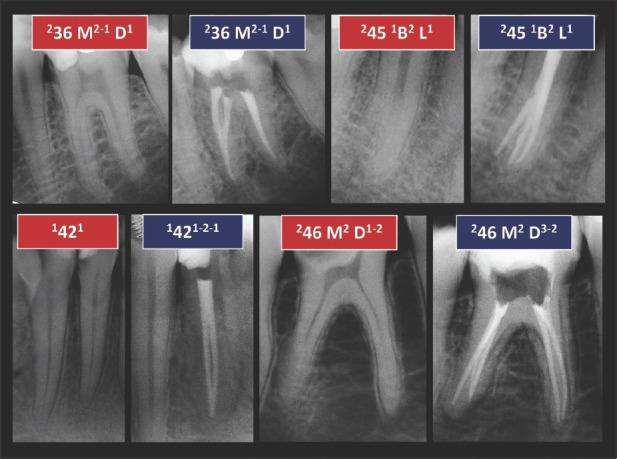

应用根管解剖分类新系统于临床实践:说明与详述。

Application of a new System for Classifying Root and Canal Anatomy in Clinical Practice - Explanation and Elaboration.

Adequate understanding and accurate characterization of normal and unusual root and canal morphology are essential requirements for successful root canal treatment. A new coding system for classifying root and canal morphology, accessory canals and anomalies has been introduced. In addition to technological advances related to experimental studies involving micro-computed tomography, the continuing clinical advances in magnification, illumination, imaging and intra-operative root canal treatment procedures have allowed clinicians to identify an increasingly wide range of anatomical variations in roots and canals in an attempt to achieve more predictable clinical outcomes. This review aims to provide a step-by-step explanation for the clinical application of the new coding system in dental practice, and to describe the anatomical variations in roots and canals for teeth scheduled for root canal treatment.

充分理解和准确描述正常和异常的牙根和根管形态是根管治疗成功的基本要求。引入了一种新的根管形态、副根管和异常分类编码系统。除了与涉及微计算机断层扫描的实验研究相关的技术进步外,放大、照明、成像和术中根管治疗程序的持续临床进展使临床医生能够识别越来越广泛的根和根管的解剖变异,试图实现更可预测的临床结果。本综述旨在为新编码系统在牙科实践中的临床应用提供逐步解释,并描述计划进行根管治疗的牙齿的牙根和根管的解剖变异。